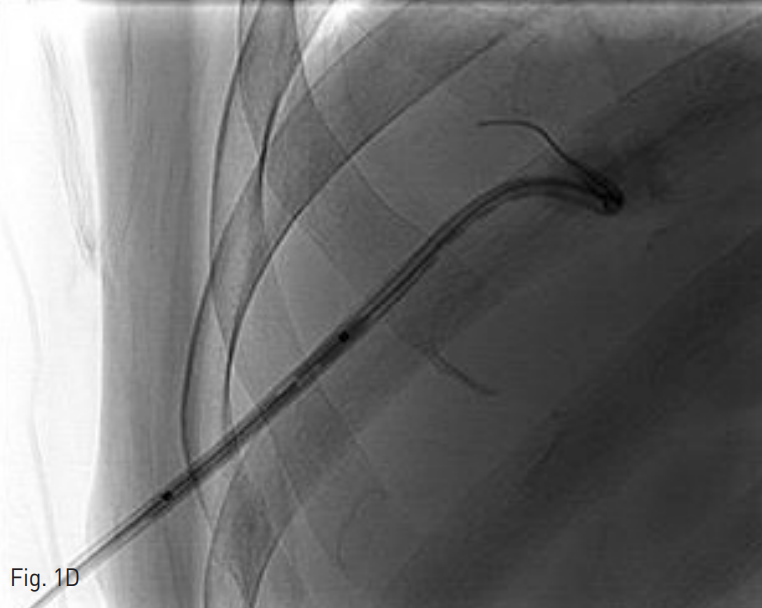

Fig. 1. A 65-year-old man who underwent pig-tail catheter insertion for the right hepatic abscess.

D. A 4mm balloon catheter was inserted via Terumo guide wire. After inflation of balloon catheter, pig-tail catheter fragment was retrieved with balloon catheter and Terumo guide wire